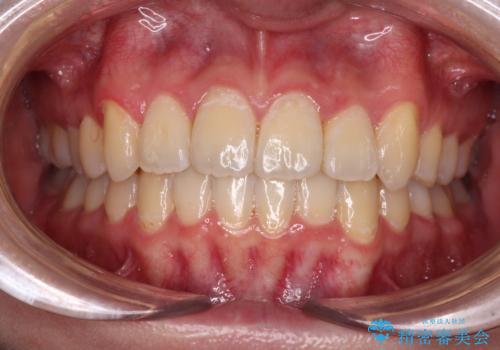

口元の突出感とデコボコがあり、上下左右の小臼歯4本を抜歯して矯正治療を行う方針としました。(右上は欠損のため計3本抜歯)

むし歯となっている歯は状態が悪く、将来的に抜歯となる可能性が高かったため、定石で抜歯させる小臼歯の代わりにむし歯となっている大臼歯を抜歯し、ワイヤー装置にて矯正治療を行うこととしました。

イレギュラーな大臼歯抜歯矯正であったため、治療期間の長期化が想定されましたが、何とか3年ちょうどで終えることができました。

今後は目立っている銀歯を中心にセラミッククラウンなどへ交換していく予定です。